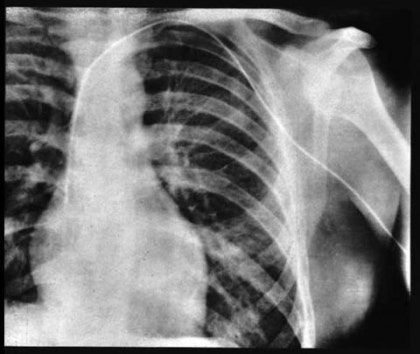

간호사는 당연히 놀라서 비명을 질렀지만 손발이 묶여있었고.. 그 동안 베르너는 조영제까지 투여 후 간호사를 풀어줌 이미 했는데 시발 어떻게 할 수도 없고 둘이 같이 X-ray실에 감   3. 노벨상킥 그렇게 X-ray실로 갔을 때 소동을 들은 베르너의 친구가 와서 카데터를 뽑으려고 함 당시 심장에 이물질이 들어가면 죽는다고 생각했기 때문에, 친구를 살리려고 한 거였음 자신을 살리려는 친구에게 베르너는 발차기를 먹여서 꼼짝 못하게 한 후 엑스레이를 통해 카테터의 끝이 심장에 도달한 것을 찍음